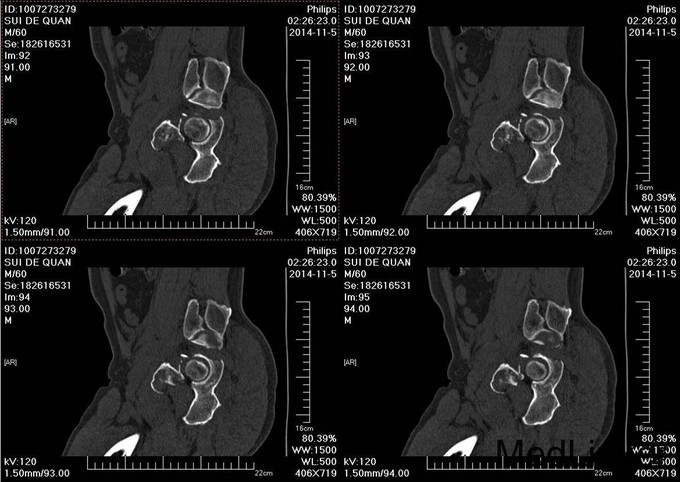

1.患者老年男性,以“车祸左髋部疼痛活动受限3天”为主诉入院。 2.现病史:患者自述于2014-11-04日晚下午7点发生机动车肇事,伤后患者急救车送往孤山二院,诊断为左髋臼骨折,当地医院未经任何治疗。急来中国医科大学附属盛京医院第五骨科创伤骨科治疗。我科以“左髋臼骨折”为主要诊断收入院。今来我院就诊,患者病来一般状态可,生命体征平稳,无发烧无发热,饮食睡眠可。

专科查体:患者平车入病房,左腿内收内旋屈曲畸形,左髋部压痛(+),叩击痛(+),骨盆分离试验阳性,活动受限,双下肢感觉未见异常,活动可,双侧足背动脉搏动可触及,双侧足趾活动灵活。

入院后急诊行左髋关节脱位复位术,左胫骨结节骨骼牵引术。术后牵引7公斤,完善相关检查后,全麻下行左髋臼骨折切开复位内固定术。术后患者生命体征平稳,卧床。术后14天拆线后出院,回当地医院继续治疗。